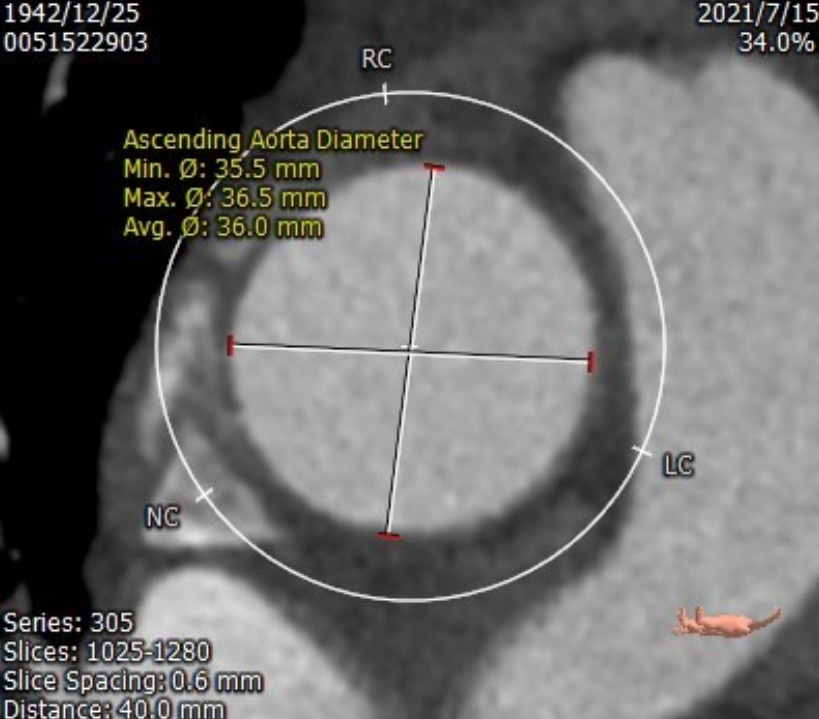

术前评估:

Ascending Aorta 35.5*36.5m

内径符合TAVI要求

该患者CT特点为:

功能性二叶瓣,左右融合,钙化极重,主要集中于无冠瓣叶,冠脉开口高度可,窦部空间可,腹主动脉轻度迂曲,右股动脉分叉位于股骨头中点,左股动脉分叉位于股骨头上1/3,拟右股动脉入路,22球囊扩张,植入26 Venus-A,该病例使用极简式介入瓣膜手术策略进行操作。